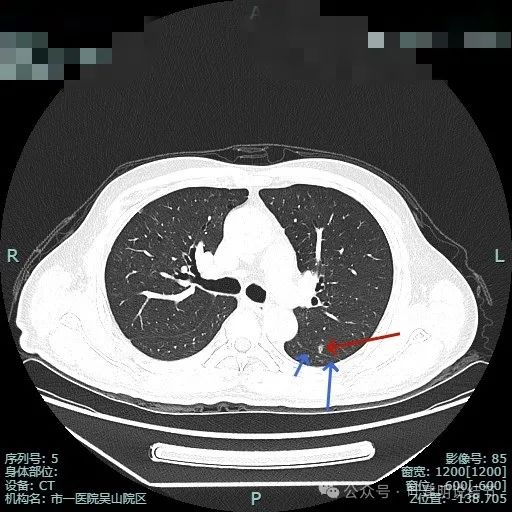

明明典型浸润性癌影像表现病理结果却是原位癌,原位癌也可表现为混合密度?

病史摘要:患者 3 个月前社区体检发现肺结节,就诊时医生考虑左上病灶基本为肺癌且倾向浸润性,因首次发现,建议口服抗炎 10 - 12 天,间隔 3 个月复查。此次复查无吸收好转及明显进展,拟手术治疗。诊疗过程:体格检查未提及。影像检查显示左上叶胸膜下混合密度结节,有血管弯征、胸膜牵拉等诸多恶性特征,下叶有次病灶。临床考虑左上叶病灶恶性且浸润性癌可能性大,建议手术。术中快速切片报腺癌

原位癌